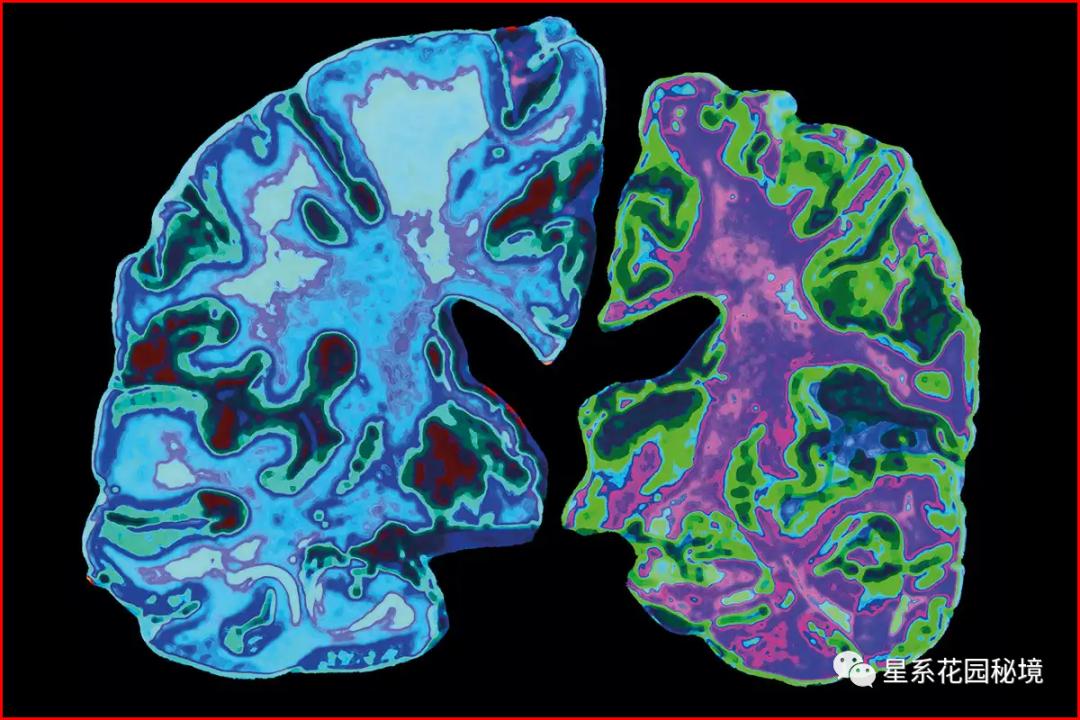

2006年发表的论文,引发了最近一项受到审查的研究,它首次确定了一种名为淀粉样β星56的蛋白质分子,是导致实验小鼠记忆丧失的原因。

这部科研结论由明尼阿波利斯的明尼苏达大学阿尔茨海默病研究的后起之秀西尔万·莱斯内博士及其上司凯伦·阿什教授和同事们撰写,随后在 2000多项 关联神经学研究中被其他研究人员引用,而这些研究人员正在寻找治疗这种毁灭性疾病的药物。也就是说,新的科研都是建立在认可明尼苏达大学科研结论的基础上进行的。十多年来,很少有人公开质疑其科学性。

但近来一些专家表示担心,他们无法在实验室复制这项研究的实验结果——重复科学实验是帮助确认研究结果的科学性的关键部分。如果其他科学家用同样的设备、材料和物理环境重复实验却得不到类似数据,该实验的结论就大概率是假的。

更令人担忧的是,十年内多个科学团队曾反复警告称,报告中使用的图像似乎是PS伪造的。他们提醒了发表这些研究的专业期刊,但直到今年6月份,自然科学期刊才对可疑论文发出了警告。

在Lesné博士的研究中,测试似乎显示,年龄较大的小鼠大脑中β星56蛋白分子的水平较高,而且它们有记忆丧失的迹象。然而,批评人士表示,这些图像中有许多看起来像是PS被篡改过的。图形软件篡改过的统计图,其实是有痕迹的(我本人作为资深图形操作者,对P过的图也是非常敏感的,其实最简单的方式是打开其文件属性栏的“最近版本信息”,如果被windows标注了Adobe Photoshop…则直接穿帮)